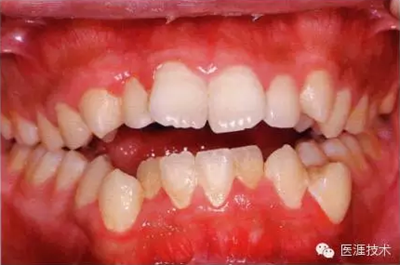

14歲男性牙齦炎的臨床圖像

26歲男性牙齦炎的臨床圖像

26歲男性。開口呼吸。混合有牙齦發(fā)紅、腫脹與纖維性肥厚。菌斑干燥牢牢黏住,刷牙難以刷掉。